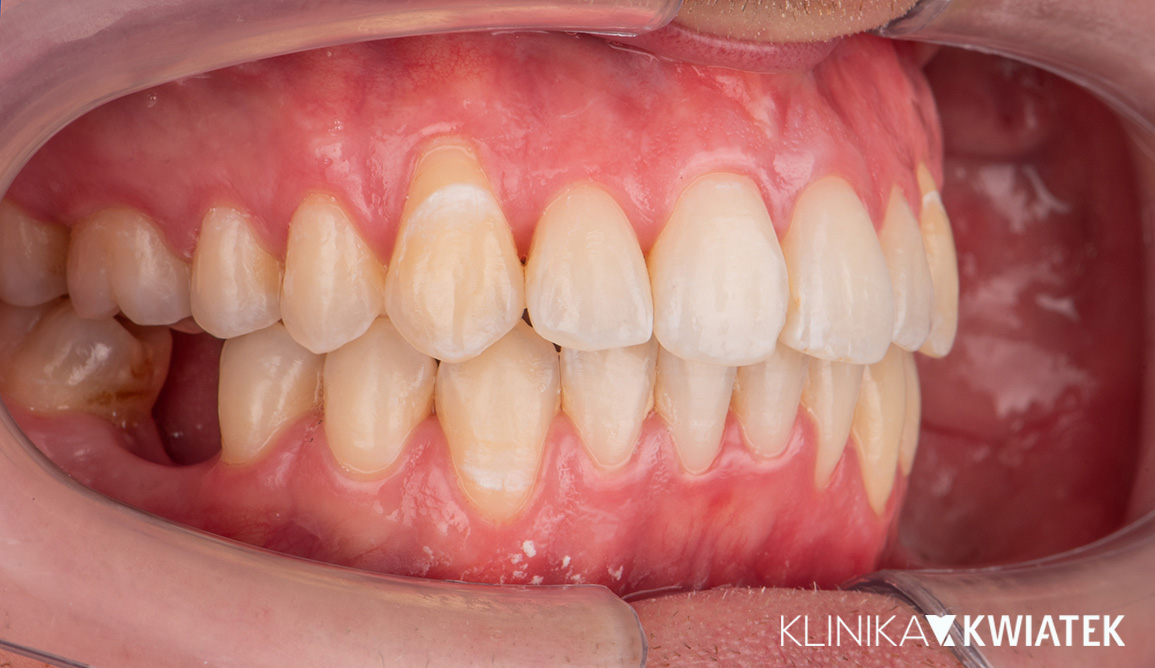

Kompleksowa metamorfoza uśmiechu – od ortodoncji po protetykę i implantologię

Pacjent zgłosił się do kliniki z problemem przetrwałych zębów mlecznych, diastemy i nierównego zgryzu, oczekując szybkiego, ale trwałego efektu estetycznego. Przeprowadzono wieloetapowe leczenie obejmujące higienizację, leczenie zachowawcze, terapię nakładkami ortodontycznymi, implantację oraz nowoczesną protetykę. Finalnym efektem jest harmonijny, biały i zdrowy uśmiech, dopasowany do rysów twarzy.